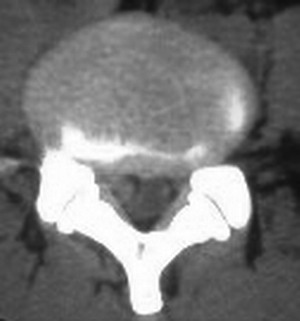

以下是引用fumaogui在2007-4-7 10:58:00的发言:[br]右侧腰4-5及骶1水平右侧神经根较对侧增粗,建议做mri排除一下神经源性肿瘤.

以下是引用zjzjr在2007-4-7 11:00:00的发言:[br]考虑腰4--5椎间盘突出长期压迫刺激致腰5神经根水肿,建议mr除外占位性病变。